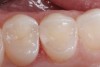

12. An occlusal view of the completed distal occlusal composite restoration on tooth No. 5.

Figure 12